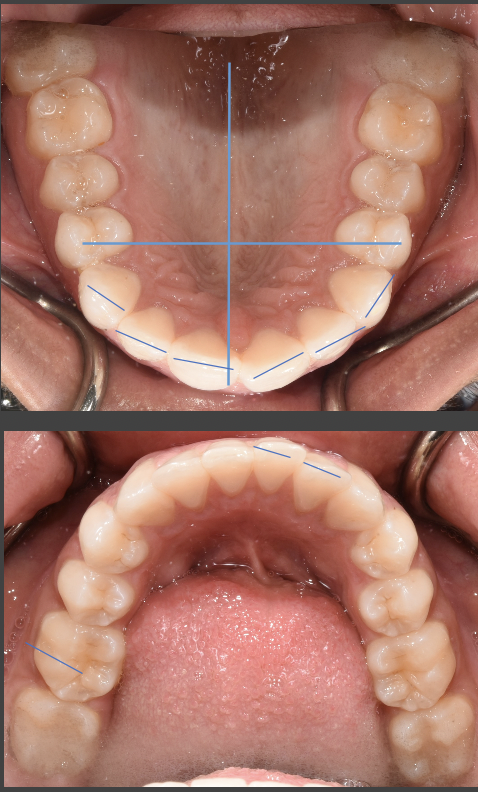

The alignment of your teeth and your molar occlusion relationship is great. Your midline looks like it is on in the picture, however the picture does not show your entire nose or eyes. The midline is aligned with the maxillary (upper) central incisors, not the mandibular (lower)and the maxillary and mandibular midlines do not have to line up with one another. As far as the "gaps" are concerned, I notice one between your maxillary central incisors that is a result of your gingival tissue creating what is called a "black triangle". This is formed when the two adjacent teeth are more bulbous creating a space near the gingiva (gums). A cosmetic or general dentist can bond the teeth with composite resin or place porcelain veneers to close that space. I would suggest whitening prior to any cosmetic procedure. Be sure to continue to wear your retainers as directed and visit your dentist for your cleanings and exam.